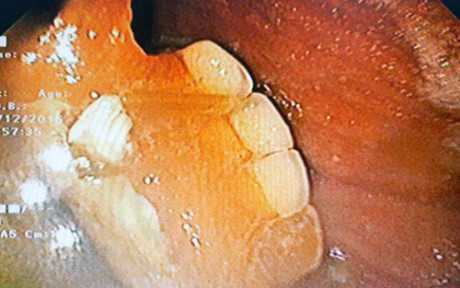

Bệnh nhân lỡ nuốt cả hàm răng giả, suýt đâm thủng dạ dày

Phát sinh cơn đau vùng thượng vị, một cụ bà 60 tuổi đến bệnh viện kiểm tra thì bất ngờ phát hiện dị vật là một hàm răng giả bên trong dạ dày.